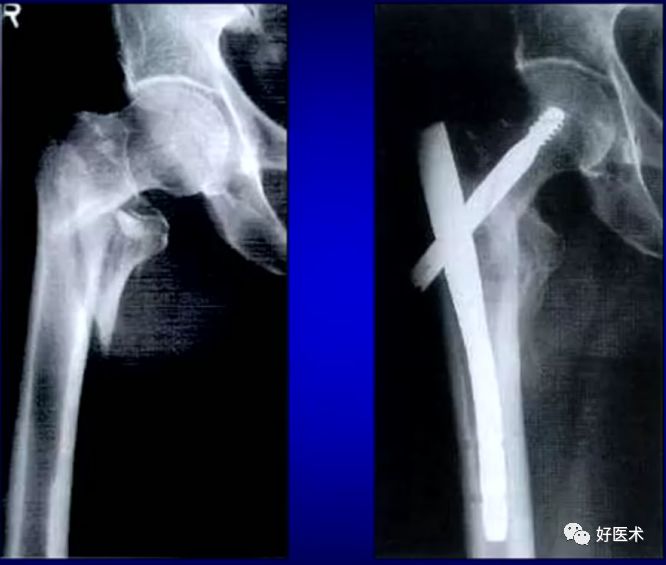

3.AO分类

1.钉板系统

六十年代后一度成为标准术式:

2.髓外DHS固定作用原理

-

如下图:极易导致固定的失败,现已作为禁忌症。

主要是临床医师对其力学特性认识不足造成的,纯属医源性因素。

3.DCS的优点:

相对DHS而言,DCS对上述情况有其明显的优点:它可根据骨折的具体情况正确选择螺钉的入点,手术操作方便。